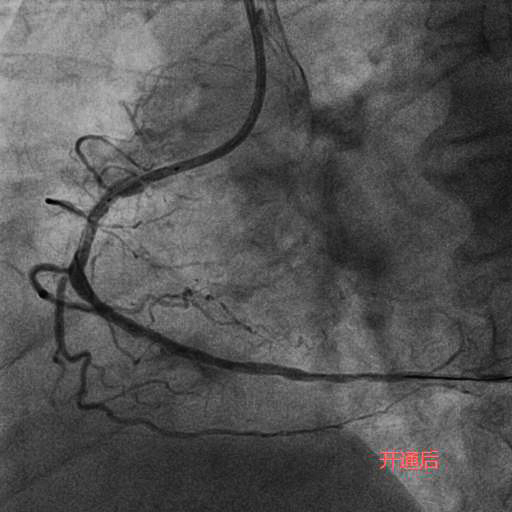

今年83岁高龄的刘老先生,退休前从事地质工作,平素身体硬朗,但近期发现快走后出现憋气症状,到某医院就诊,冠状动脉造影检查为三支病变,前降支(LAD)、回旋支(LCX)、右冠状动脉(RCA)均为完全闭塞病变且伴重度钙化。在经过近一个小时的尝试后,闭塞血管未开通,建议药物治疗。但药物治疗并未缓解刘老先生的症状,心功能反而一步步下降。后来患者及家属抱着极大的期望去某著名心脏专科医院就诊,经过半个小时的尝试后开通失败,并告知患者家属这样的血管不可能开通,冠状动脉搭桥术是唯一的出路。但是搭桥手术对于一位83岁高龄的老人来说无疑是一个艰难巨大的挑战。两次失败手术的打击使得刘老先生的身体状态每况愈下,稍事活动就气喘吁吁,逐渐对生活失去了信心。后来家属辗转打听到北京潞河医院心内科翟光耀主任团队致力于冠状动脉复杂手术,抱着最后一搏的想法,在经过两个月的药物调整后能耐受再次手术的前提下,刘老先生再次躺在了手术台上。术中,冠状动脉造影结果让翟光耀主任团队意识到了这次手术的难度之大,风险之高。三支主干闭塞,之前手术开通失败已造成血管近端夹层,闭塞的血管(尤其是RCA)全程重度钙化,近乎全程闭塞,开通血管无疑在花岗岩上开凿隧道。在经过近4个小时的不懈努力,团队终于成功开通了难度最大的RCA并植入支架,观察一天后顺利出院。 一个月后,刘老先生闭塞的LAD也成功开通。现在,刘老先生身体恢复良好,如获新生!

李奶奶今年92岁高龄,两年前曾因“急性心肌梗死”就诊于某医院,接诊专家考虑患者年龄大,合并症多,冠状动脉介入操作风险高,建议药物治疗。近半个月,李奶奶的胸痛症状频繁发作,药物治疗效果不佳,经过病友的介绍,家属选择了潞河医院翟光耀主任团队。在心脏监护室医护人员的精心治疗和护理下,李奶奶心功能改善,肺部感染得到控制,可以耐受手术。术中,冠状动脉造影显示LAD弥漫重度狭窄,RCA完全闭塞伴重度钙化。在经过近两个小时的不断尝试及努力后,闭塞的RCA成功开通,“介入无植入”未植入支架,血管成功修复。术后李奶奶恢复良好,顺利出院。